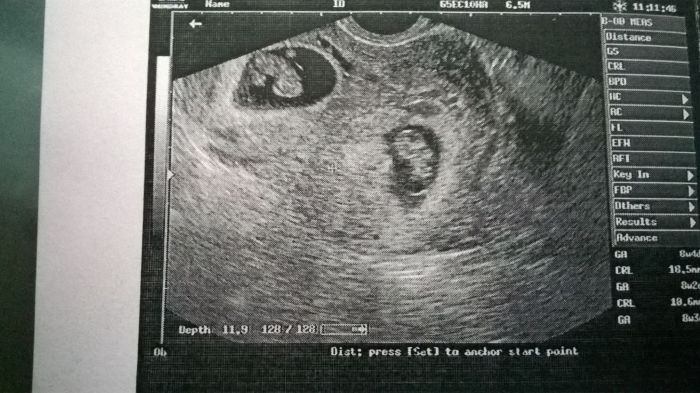

[990910] už jsem tu

nařadu jsem šla až v poledne, ale počkat si stálo za to

když mi dělala ultrazvuk, tak nevěřila vlastním očím, mám tam dvě miminka

když jsem to viděla, tak se ptám: a jsou obě živý??

takže syndrom mizejícího dvojčete nebyla správná diagnóza

prý ještě nemusel být vidět v 6 týdnu, když jsem byla na pohotovosti, protože ten jeden je vidět hůř, ale je tam, srdíčko mají obě, odpovídají stáří 8+4 a vypadají krásně živě

odcházela jsem v rozpoložené náladě, furt se v duchu smála

když jsem to ukázala manželovi, tak se taky začal smát

přikládám fotečku